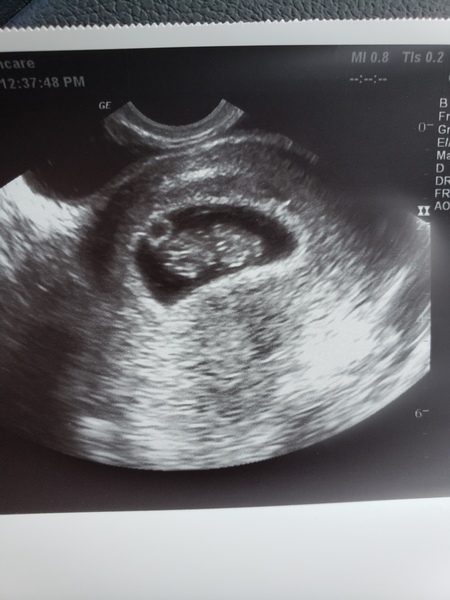

Finally saw the heartbeat today! 140bpm. I thought I was only 8 weeks but doctor measured me at 9 weeks exactly. Was worried because I had 2 days of spotting and light cramping but seeing that heart flicker was the best feeling. Seeing my 260 pound manly man cry like a baby was pretty priceless too Grin

I too got to see a little heartbeat yesterday. It really is the most wonderful experience.

Dates came in at 6+6 which is what I was expecting 😁

Scan pictures are gorgeous 😍 makes me both nervous and excited for mine!